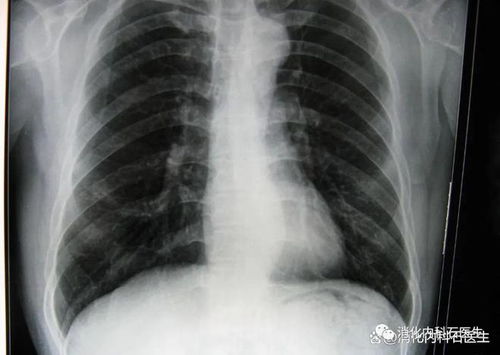

在X光片上,医生们惊讶地发现张先生的肺部竟然有一个金属异物——一个鱼钩,这个鱼钩位于张先生的右下肺叶,显然已经存在了一段时间,这一发现立即引起了医生们的警觉,他们迅速将张先生转入急诊室进行进一步的检查和评估。

急诊医生立即对张先生进行了全面的体检,并安排了CT扫描以更清晰地显示鱼钩的位置和周围的情况,CT结果显示,鱼钩已经穿透了张先生的肺部,并可能导致了局部的感染,医生们迅速制定了手术计划,准备将鱼钩取出,以防止其进一步移动并造成更严重的后果。